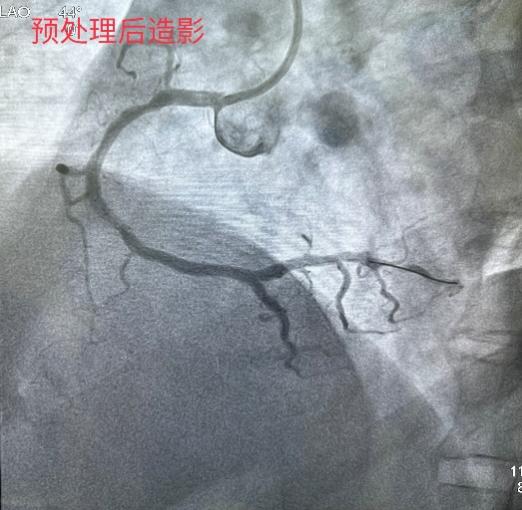

5月31日经过充分的术前准备,雷新军教授带领景林德博士和李瑞峰医生按照预定方案为患者实施了手术。冠脉造影示:RCA 2段节段性狭窄约25%,末端狭窄约90%,为不稳定斑块,血流TIMI 3级(图2a)。决定干预右冠:6F SAL1.0指引导管到位后,先操控Sion导丝通过病变至LV末端,然后再沿导丝送入血管内超声(intravenous ultrasound,IVUS)检查,结果显示RCA 2段末狭窄最重部位血管面积为2.30 mm2,斑块负荷为85%,手术指征明确(图2b)。首先,使用NC Balloon 3.0 x 15 mm 20 atm预扩张靶病变,造影示残余狭窄约25%,再在IVUS指导下植入Xinsorb BRS 3.5 x 28 mm,随后采用NC Balloon 3.5 x 9 mm 16atm逐段后扩张,造影显示支架充分膨胀,血流TIMI 3级(图2c-g)。最后,进一步使用IVUS评估手术情况,结果显示:支架充分膨胀,贴壁良好,支架远近端未见夹层,血管面积为8.01 mm2,手术效果非常满意(图2h)。术中患者无特殊不适,术后病人安返病房。

图2 经皮冠脉介入治疗